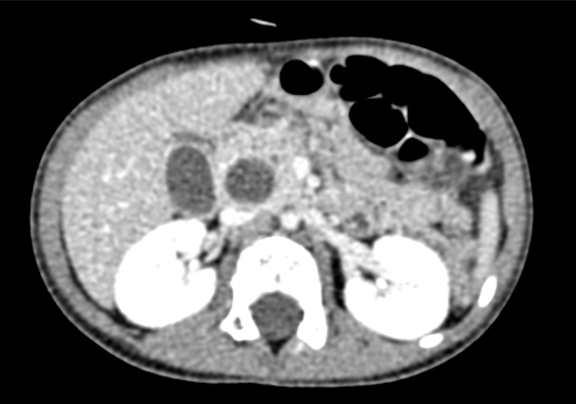

术前CT检查:

平衡期

上腹部动态三维成像(增强)CT:诊断意见:符合胆总管囊肿胆囊炎可能性大。